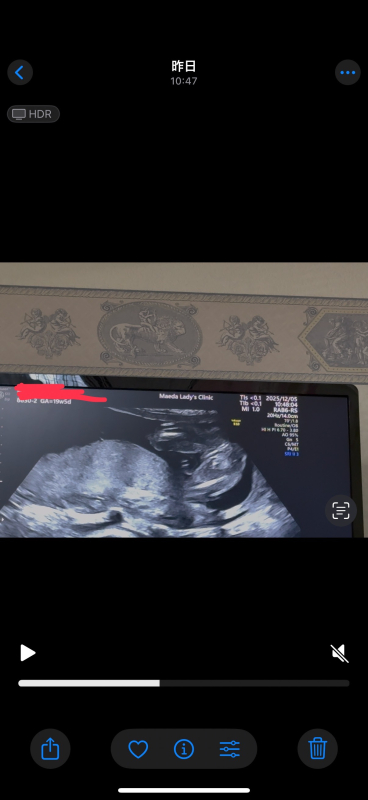

21週になりました!

ですが、まだ性別がわかりません。

いつもエコー見て検索魔になってしまい。

もし分かるのであれば教えて欲しいです

お腹の赤ちゃんの性別についてですね。

なので断言はできませんが、足と足の間男の子シンボルがはっきりと映っていなそうに感じたのと割れ目が見られるようにも思いましたので、女の子の可能性があるのではと思いました。

しかしはっきりとはわからないため、また次の健診の際に先生へご確認ください。